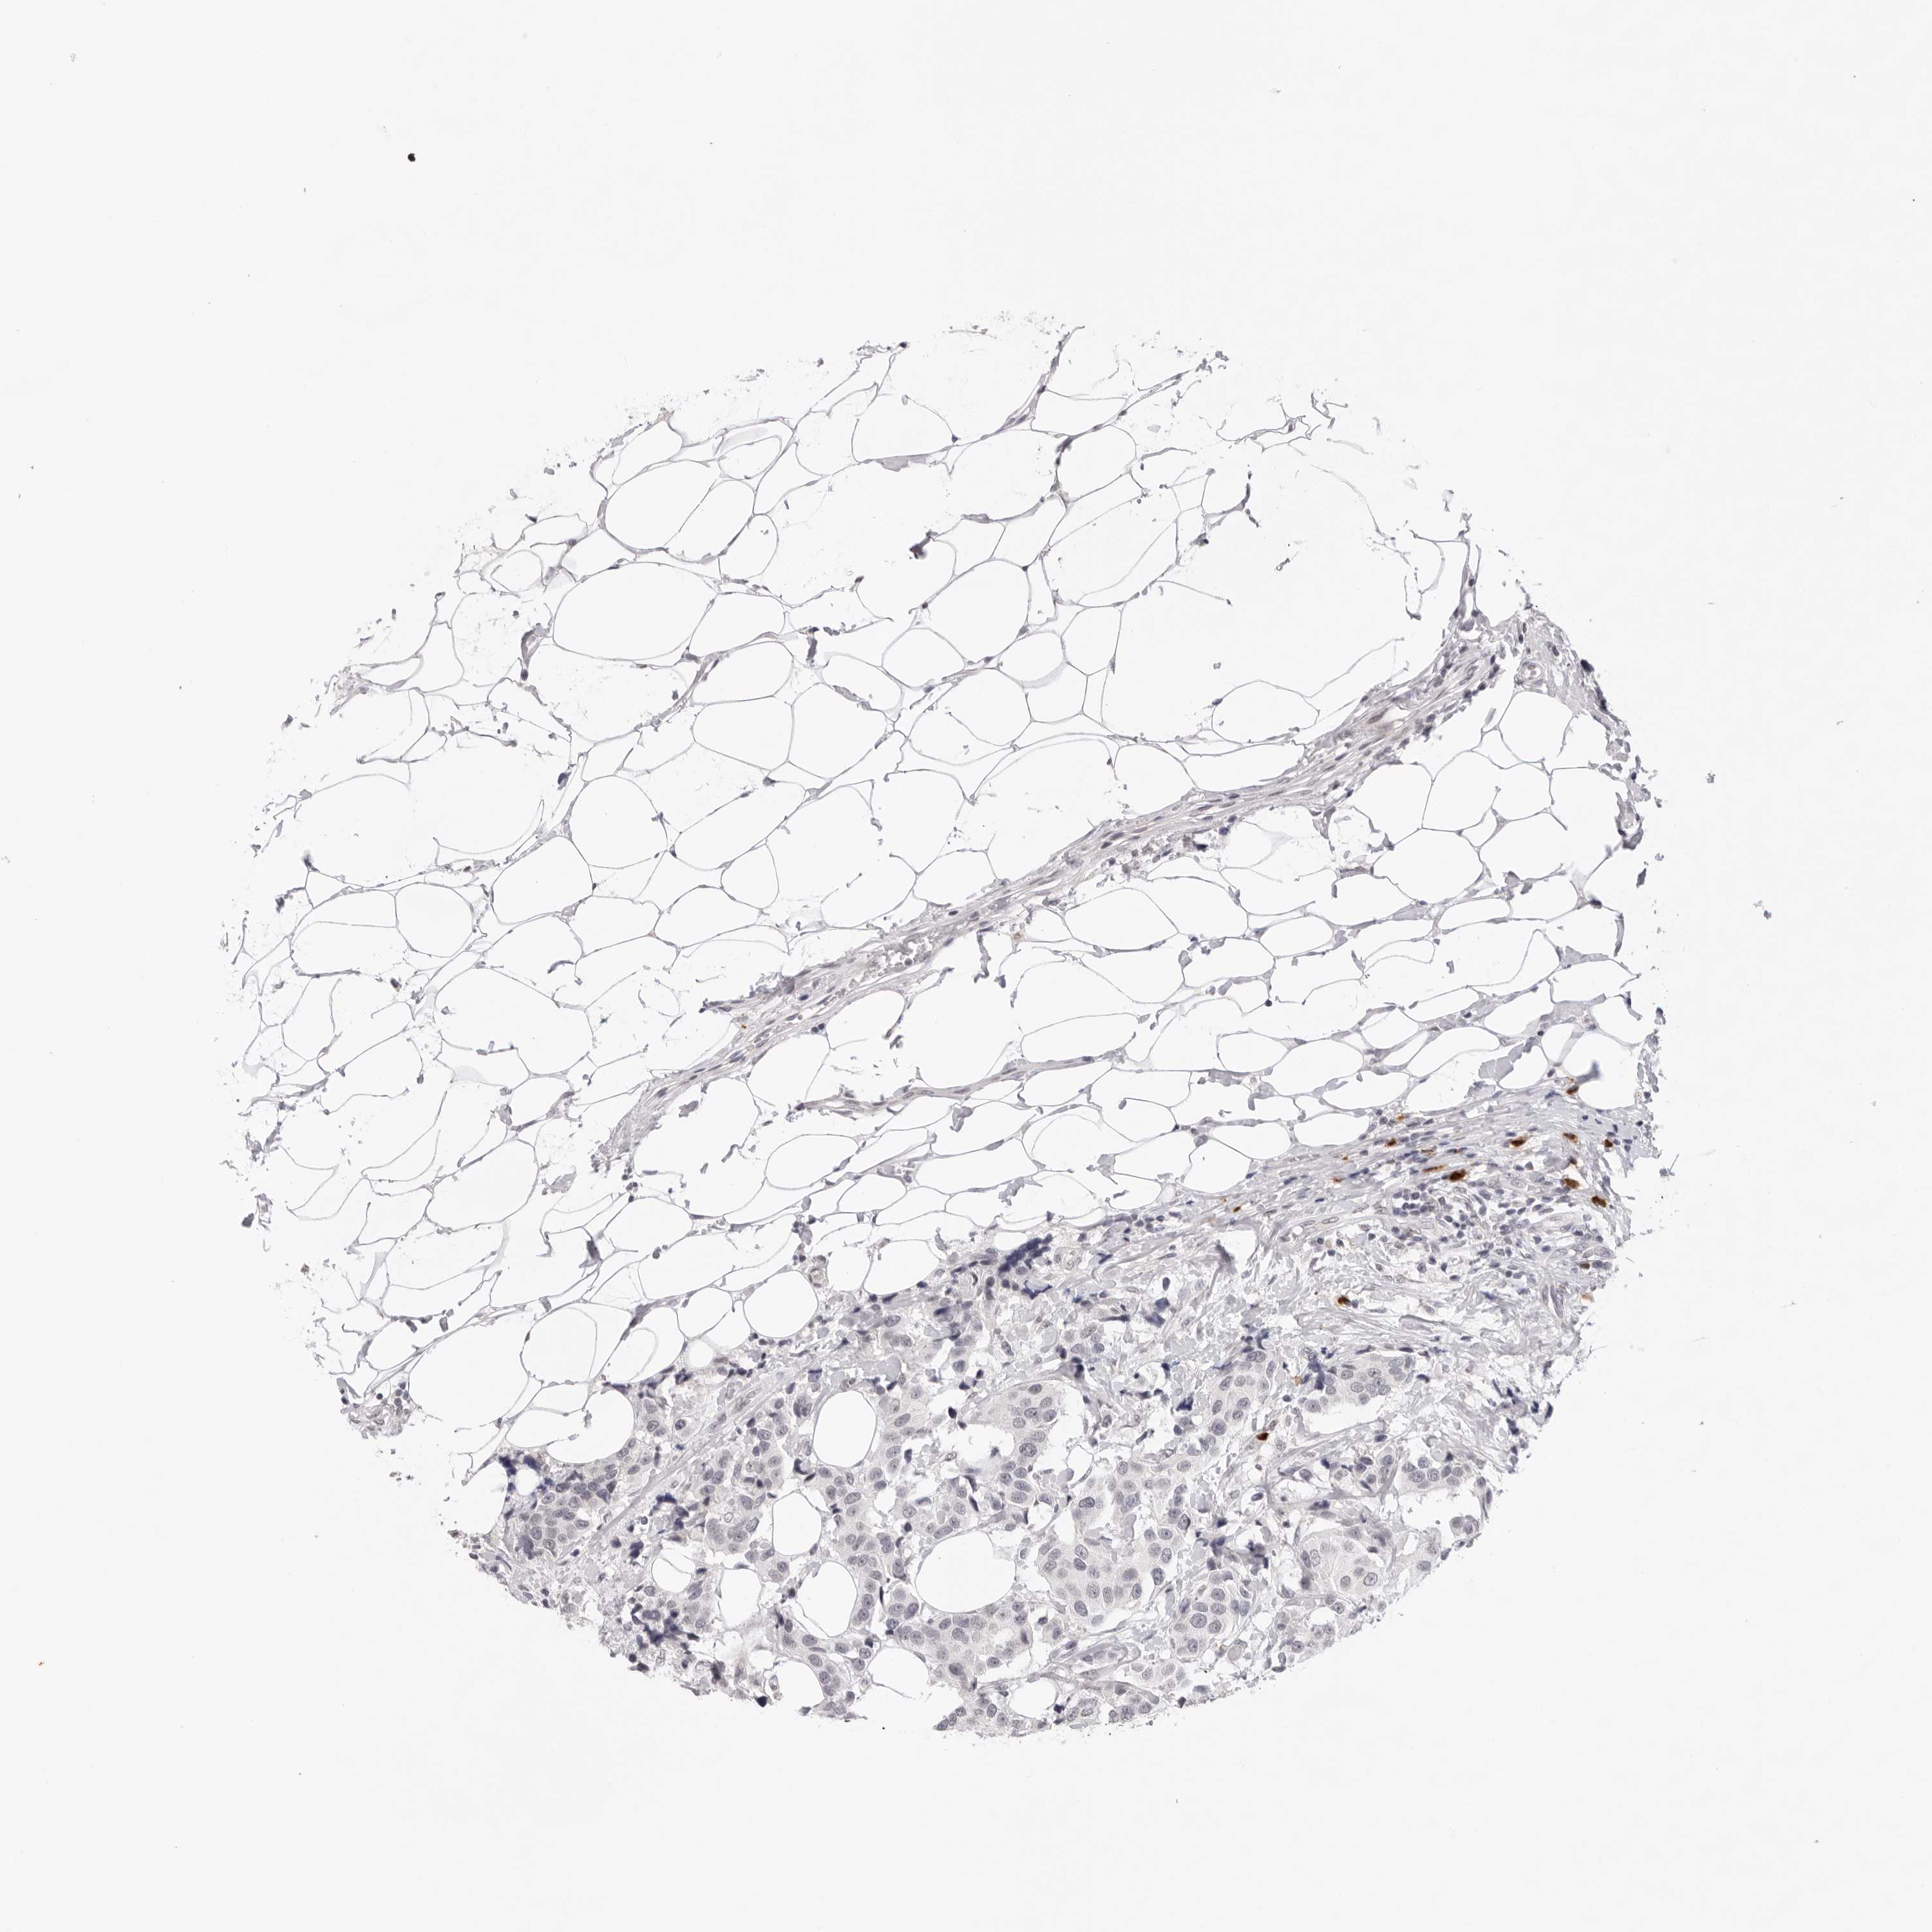

CANCER BREAST CANCER Show tissue menu

BRCA TCGA BRCA VALIDATION PROTEIN EXPRESSION

Breast cancer

Human cancer

Breast invasive carcinoma